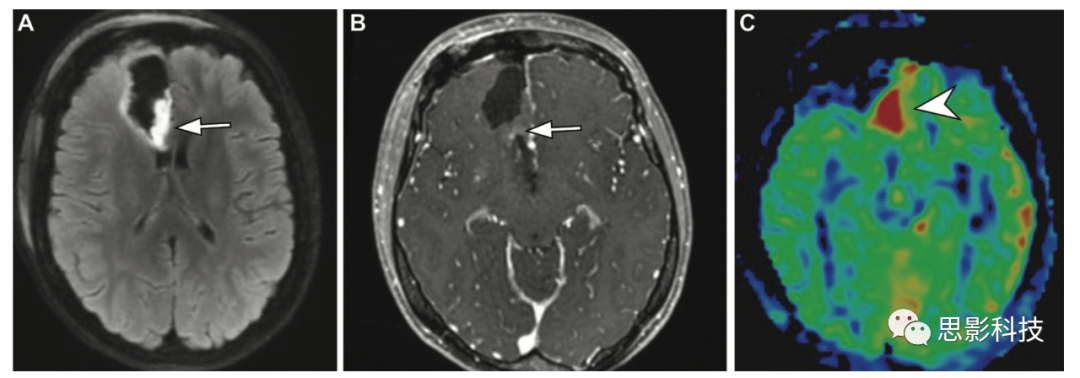

神經(jīng)膠質(zhì)瘤 ASL定量測(cè)量有助于區(qū)分高級(jí)別膠質(zhì)瘤和低級(jí)別膠質(zhì)瘤,高級(jí)別膠質(zhì)瘤因新生血管而顯示高TBF相對(duì)血流值(12),低級(jí)別膠質(zhì)瘤顯示低TBF(E5)Shen等人的研究表明,高級(jí)別膠質(zhì)瘤的絕對(duì)TBF和相對(duì)TBF均顯著高于低級(jí)別膠質(zhì)瘤(絕對(duì)TBF, 73.93±23.74 vs 38.97±17.47;相對(duì)TBF, 2.021±0.611 vs 0.971±0.268;P<0.001)。一項(xiàng)薈萃研究為ASL在膠質(zhì)瘤的術(shù)前分級(jí)診斷的準(zhǔn)確性提供了證據(jù)。研究表明,基于ASLDSC的灌注指標(biāo)具有良好的相關(guān)性和互換性。

12 一例40歲女性高級(jí)別膠質(zhì)瘤,右側(cè)偏癱15天。(AB)軸位FLAIR圖像(A)顯示左側(cè)額葉病變(箭頭),ASL(B)顯示高信號(hào)(箭頭)。(C)3個(gè)月后獲得的軸位增強(qiáng)后T1加權(quán)像顯示較大的壞死性病變(箭頭),周圍有不規(guī)則強(qiáng)化,與膠質(zhì)母細(xì)胞瘤相關(guān)。

治療反應(yīng)評(píng)估 高級(jí)別膠質(zhì)瘤的治療反應(yīng)評(píng)估是一個(gè)主要的挑戰(zhàn),特別是在區(qū)分在有新的或Gd強(qiáng)化增加的患者中,放射引起的壞死和復(fù)發(fā)的腫瘤。ASL有助于區(qū)分有新的或Gd強(qiáng)化增加的情況,因?yàn)榉派湫詨乃劳ǔ1憩F(xiàn)為低CBF,而大多數(shù)復(fù)發(fā)腫瘤表現(xiàn)為高CBF(15、16)。據(jù)報(bào)道,ASL MRI在區(qū)分腫瘤復(fù)發(fā)和放射性壞死方面具有與DSC MRIPET相似的診斷性能,在高級(jí)別膠質(zhì)瘤中可能更準(zhǔn)確,特別是存在混合放射性壞死區(qū)域(敏感度為94%)DSC MRI受血腦屏障破壞的T1T2效應(yīng)和易感性偽影的影響,而這些因素對(duì)ASL影響較小。

15 一例59歲男性因肺癌中樞神經(jīng)系統(tǒng)轉(zhuǎn)移而接受放射治療后發(fā)生放射性壞死。(A)軸位增強(qiáng)的T1加權(quán)像顯示邊緣不均勻強(qiáng)化,左側(cè)中央旁小葉有不規(guī)則病變(箭頭),磁敏感加權(quán)成像顯示周圍有廣泛的血管性水腫(未顯示)。(B)ASL MRI顯示受影響區(qū)域腦血流量降低,提示放射性壞死。

16 一例53歲女性在晚期高級(jí)別膠質(zhì)瘤術(shù)后影像隨訪時(shí)殘留或復(fù)發(fā)腫瘤。(A,B)軸位彌散加權(quán)(A)和高空間分辨率增強(qiáng)T1加權(quán)(B)顯示不均勻強(qiáng)化和沿手術(shù)腔后緣的受限擴(kuò)散(箭頭),沿后內(nèi)側(cè)邊緣有結(jié)節(jié)狀和不規(guī)則的局灶增厚。

(C)ASL MR圖像顯示外科手術(shù)腔后內(nèi)側(cè)緣高CBF,伴有局灶結(jié)節(jié)增厚(箭頭),表明存在復(fù)發(fā)或殘留腫瘤。